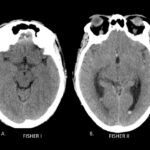

La escala de Fisher es un índice de riesgo de vasoespasmo basado en un patrón de hemorragia definido por tomografía sin contraste (TC) (ver Tabla 5), y la escala de Fisher modificada (también conocida como escala de Classen) es un índice similar de riesgo de isquemia cerebral tardía por vasoespasmo (ver Tabla 6).

| Tabla 5. Escala de Fisher en tomografía para la valoración del riesgo de vasoespasmo en la HSA | |

| Grado | Patrón de HSA en TC de cerebro sin contraste |

| 1 | No HSA o hemorragia intraventricular (HIV) |

| 1 | HSA difusa o capa fina en todas las capas verticales (en cisura interhemisférica, cisterna insular, cisterna ambients) de menos de 1 mm de espesor |

| 2 | Hematoma localizado y / o capas verticales de 1 mm o más de espesor |

| 3 | Hematoma intracerebral o intraventricular con sangre subaracnoidea difusa o sin sangre |

Fisher CM, Kistler JP, Davis JM. Relation of cerebral vasospasm to subarachnoid hemorrhage visualized by CT scanning. Neurosurgery.

Fig. 1a. Escala de Fisher modificado en TC de cerebro sin contraste, cortes axiales. A. Fisher I y B. Fisher II.